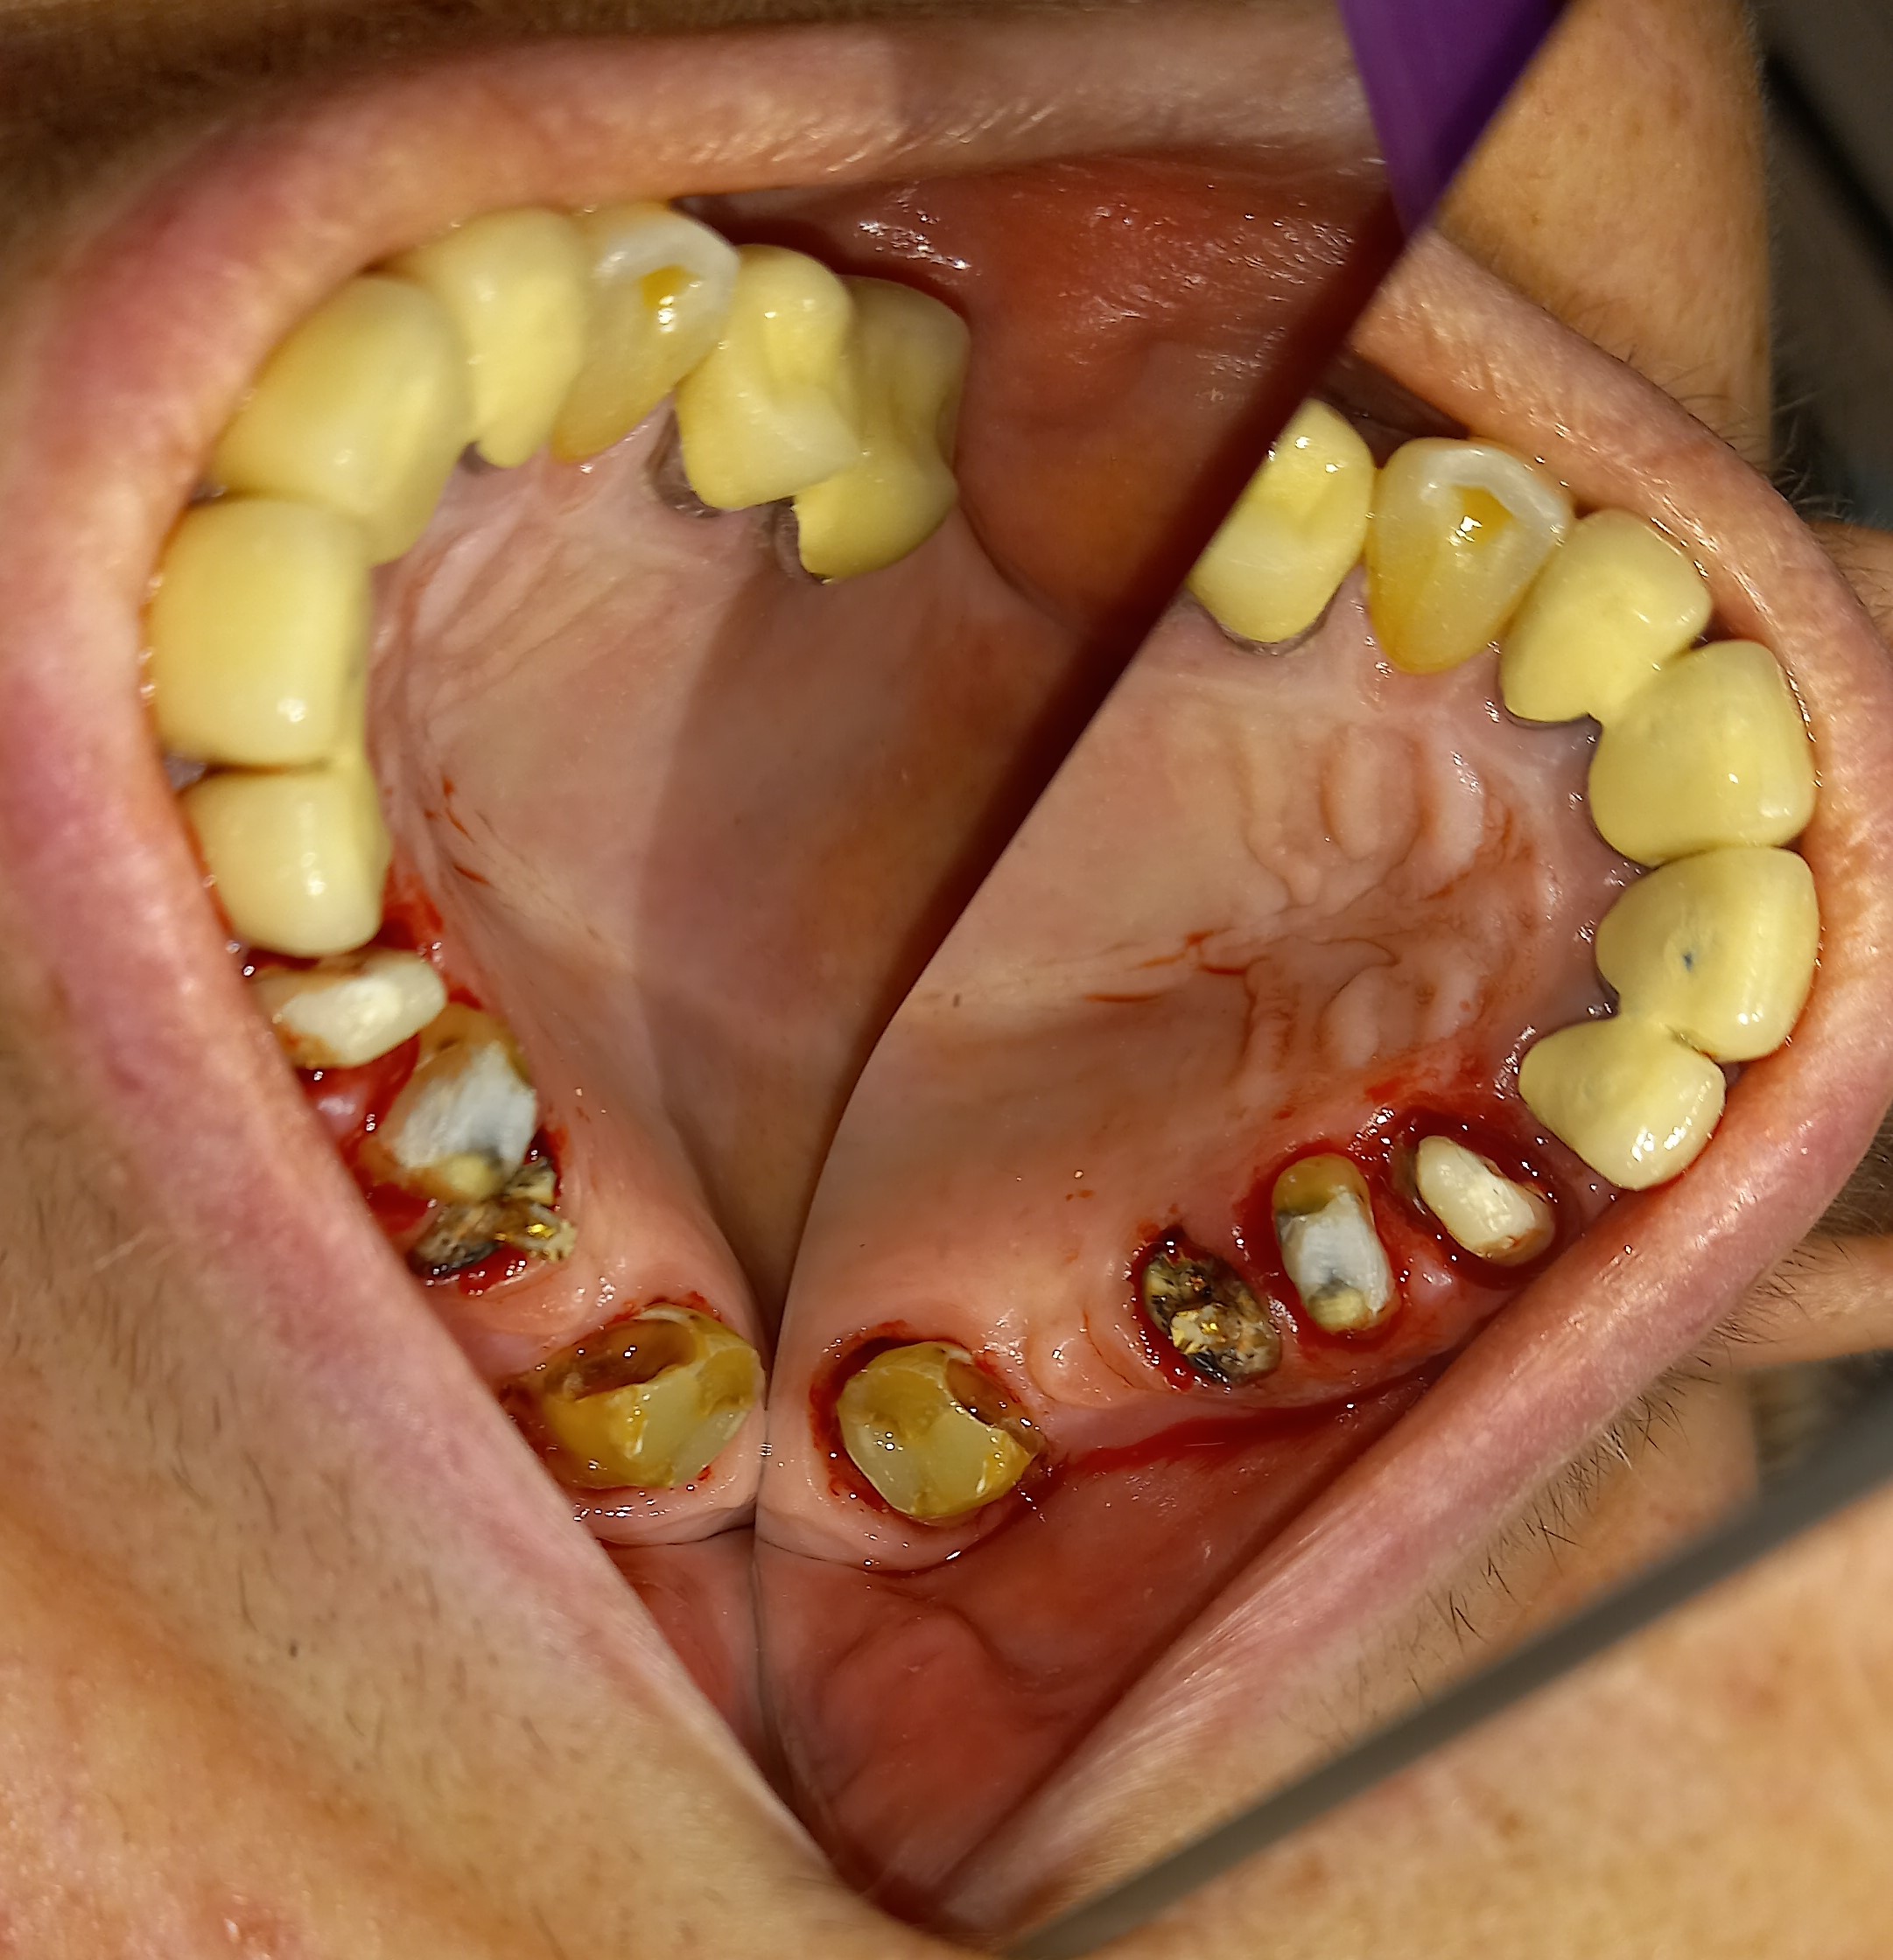

Ο ασθενής είχε πάρα πολλά χρόνια να επισκεφτεί τον οδοντίατρο. Πρόκειται για ένα απαιτητικό περιστατικό, κατά το οποίο ο ασθενής ήταν πολύ συνεργάσιμος καθώς ήθελε να αποκτήσει ένα όμορφο και λαμπερό χαμόγελο. Αρχικά εξάχθηκαν όσα δόντια δεν μπορούσαν να διατηρηθούν πλέον στο στόμα του ασθενή. Στη συνέχεια απονευρώθηκαν τα περισσότερα δόντια και ακολούθησαν ανασυστάσεις όλων των δοντιών. Εφόσον είχε αποκατασταθεί η φλεγμονή των ούλων λήφθηκαν αποτυπώματα και στάλθηκαν στον οδοντοτεχνίτη ο οποίος κατασκεύασε ολοκεραμικές θήκες, οι οποίες ήταν ενωμένες μεταξύ τους (ολοκεραμικό πέταλλο). Ο ασθενής φορούσε προσωρινή γέφυρα στο μεσοδιάστημα που χρειάστηκε ο οδοντοτεχνίτης να κατασκευάσει τη μόνιμη προσθετική εργασία.

ΠΡΙΝ

Ενδιάμεση κατάσταση αφού ολοκληρώθηκαν οι ανασυστάσεις δοντιών